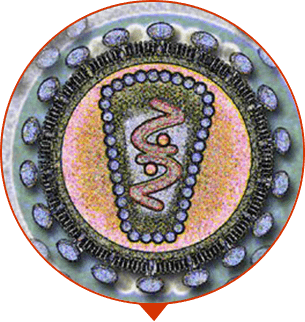

Magnesio

afecta positivamente el nivel de testosterona en el cuerpo. Tiene un efecto antiinflamatorio, protege la próstata de infecciones, mejora el funcionamiento de la próstata y la vejiga.

Vitamina E

protege contra el cáncer de próstata y vejiga, apoya el funcionamiento normal de los órganos reproductivos y previene la infertilidad masculina.

Vitamina B6

normaliza el equilibrio hormonal, mejora la inmunidad, mejora la función cardíaca, restaura el funcionamiento de las células de la próstata. Recomendado para mejorar la motilidad de los espermatozoides.